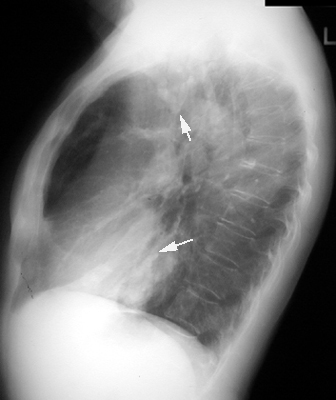

Bronchial Cast

"Gloved finger" appearance. Branching density. Inspissated mucus, distends bronchi giving such an appearance.